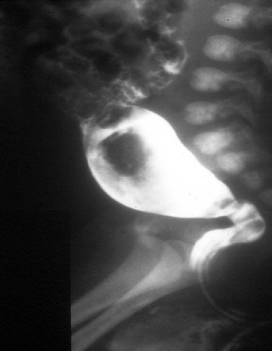

▷ 钡剂灌肠(Barium Enema)

- 无神经节细胞段与近端结肠口径差别、扩张段、狭窄段及移行段改变

- 结肠炎时粘膜锯齿状改变

- 24小时后钡剂滞留

操作简单,方法普及

新生儿确诊率80%

短段型不易诊断